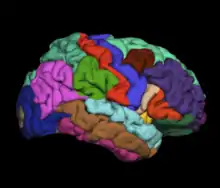

1) Development of an automated atlas of the human cerebral cortex (Desikan-Killiany Atlas in FreeSurfer),[11] and its role as a quantitative biomarker for neurodegeneration in Alzheimer's disease.